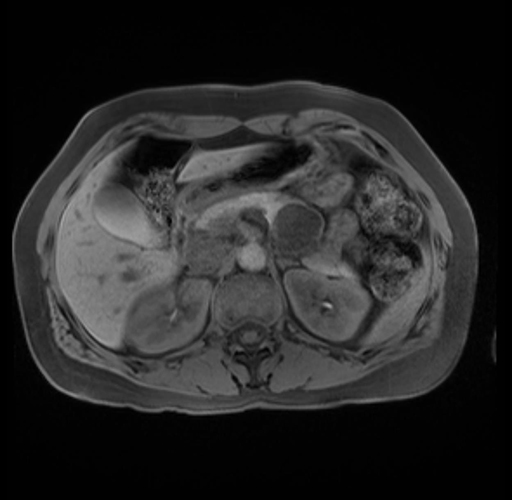

Imaging Analysis

Look through the patient's CT scan to identify any areas of concern for the necessary procedure.

Based on your CT findings, which issue(s) are present and would give reason for "planned slowing down moment(s)" in this case?